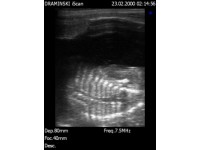

DISTINGUISHING BETWEEN GESTATION SACS AND INTESTINES

This quick video clip illustrates the difference between the appearance of gestation sacs and intestines on a canine or feline ultrasound scan. Note the 'hamburger' shape of the intestines, which would appear tubular with rotation of the probe by 90 degrees. The pregnancy sacs, on the other hand, are circular at this early stage (30 days) and would maintain their distinct borders even with rotation of the transducer.